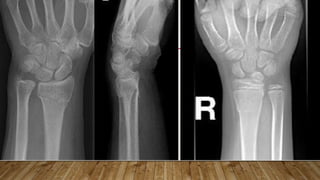

This document discusses radiology and the use of x-rays. It begins with an introduction to radiology and x-rays, noting their importance as the "father of medical investigations." It then discusses anatomy as seen on radiographs and whether x-rays are enough. The document goes on to compare gross views to radiological views, noting what each can and cannot show. It highlights important figures in the development of radiology, from x-rays to CT, MRI, and ultrasound. Specific anatomical structures visible on upper and lower limb x-rays are listed. The document concludes by discussing how pathologies appear on x-rays and the importance of clinical history and knowledge when interpreting radiological images.